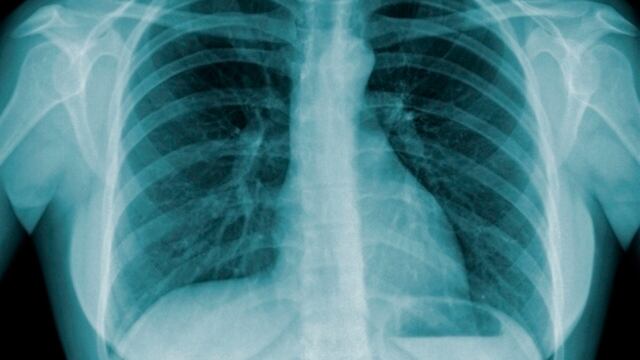

No Dia Mundial de Combate à Tuberculose, comemorado na última quinta-feira, a Sociedade Brasileira de Urologia (SBU) alertou a população que a doença, quando não diagnosticada e tratada ou quando o tratamento é suspenso, pode provocar complicações em outros órgãos do corpo, entre as quais a tuberculose geniturinária, uma das consequências mais graves da tuberculose pulmonar.

O presidente da SBU, Alfredo Canalini, explicou que, no país, a porta de entrada do bacilo de Koch, causador da tuberculose, é o pulmão. Na grande maioria das vezes, a doença começa com uma infecção pulmonar que pode provocar alguns sintomas que o paciente acaba negligenciando, como febre, tosse persistente e perda de peso.

“Esse bacilo de Koch, na medida em que ele vai colonizando o pulmão, os gânglios linfáticos, ele pode chegar até a corrente sanguínea. Quando isso acontece, ele pode se alojar em diferentes partes do corpo”, disse. As consequências podem ser tuberculose óssea e tuberculose urinária. A tuberculose pode ser prevenida com a vacina BCG nos recém-nascidos.